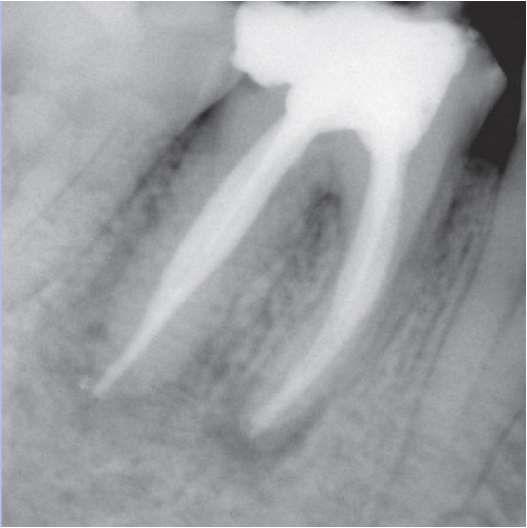

Before

Before Root Canal treatment